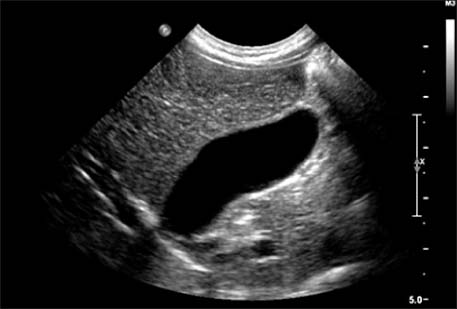

Fig. 2

Ultrasonography performed at the emergency room shows multiple gallbladder sandy stones with sludge (case 2).

Ultrasonography after 6 weeks of conservative treatment shows the disappearance of previous gallbladder stones (case 2).